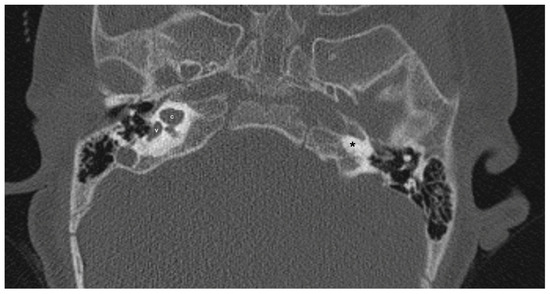

LCVD was detected in six ears of three patients, while isolated LSCCH was detected in six ears of three patients. No additional malformations were detected in these patients’ cochleae or other inner ear structures (Figure 5). Cochlear nerve anomalies were observed in 11 patients with a history of congenital SNHL. Among these, seven had bilateral hypoplasia, two had isolated right cochlear nerve hypoplasia, one had isolated left cochlear nerve aplasia, and one had left cochlear nerve hypoplasia while the right cochlear nerve could not be distinguished. Within this group, only one patient showed no cochlear anomaly.

Figure 5.

A case of bilateral lateral semicircular canal-vestibular dysplasia (LCVD). Both vestibules (v) are dilated and form a common cavity with the lateral semicircular canals (LSCC). The cochlea (c) can be normal (partially shown). IAC, internal acoustic canal.